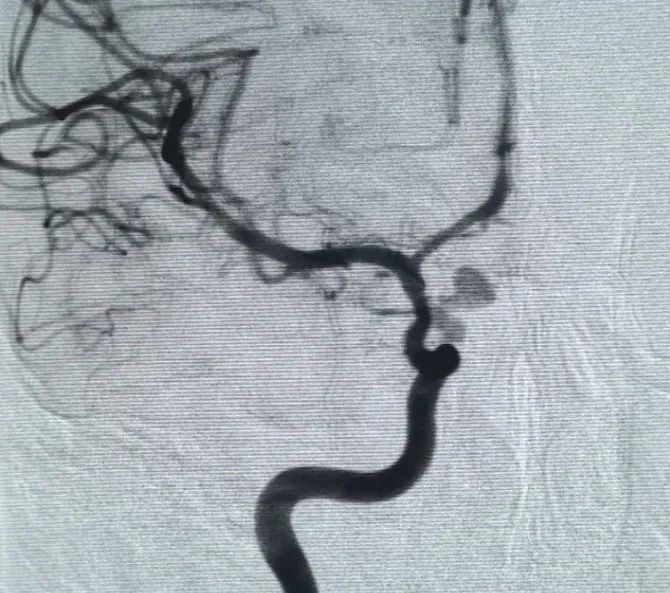

Diagnosi: aneurisma dell'arteria oftalmica del segmento C6 dell'arteria carotide interna sinistra

L'accesso vascolare è stato stabilito tramite puntura dell'arteria femorale e un Perdenser®La bobina 3D da 6mm × 20 cm è stata inizialmente utilizzata per formare un cestello, ottenendo una posizione stabile della parete e fornendo un supporto intrasaculare sicuro. A seguire l'inserimento di un Perdenser®Bobina 3D da 6mm × 15 cm per interrompere il flusso sanguigno all'interno del sacco figlia lobulato.

Un Perfiller®3mm × 6 cm bobina espandibile e un Perfiller®La bobina espandibile di 3mm × 2 cm è stata quindi posizionata per completare l'occlusione del collo. Successivamente, una Nuva®Flow Diverter (TJED-D-5.0-16) è stato consegnato e distribuito attraverso il collo dell'aneurisma. L'angiografia di follow-up in entrambe le viste antero e laterale ha confermato una copertura eccellente, una buona apposizione della parete e una chiara radiopacità, con un netto ristagno di contrasto.